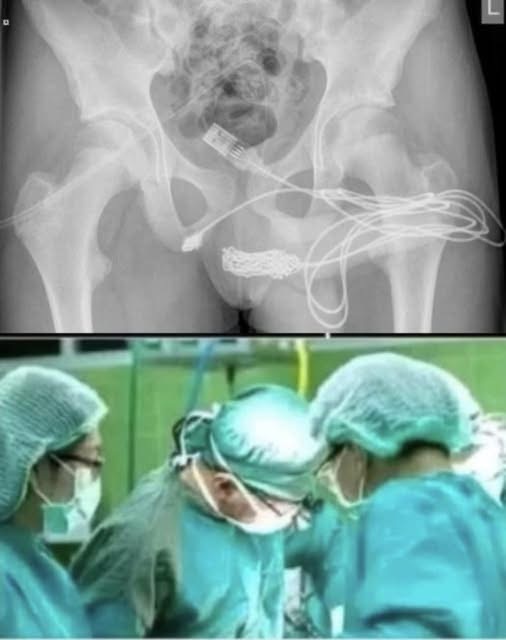

A shocking case has gone viral on social media after a young girl had to be rushed to the hospital for a bizarre and dangerous act. According to reports, the teenager inserted a pen into her private parts, which led to severe internal injuries and complications.

Doctors performed an emergency surgery to remove the object and stabilize her condition. Medical experts are now warning young people not to experiment with foreign objects, as it can lead to life-threatening infections or permanent damage.